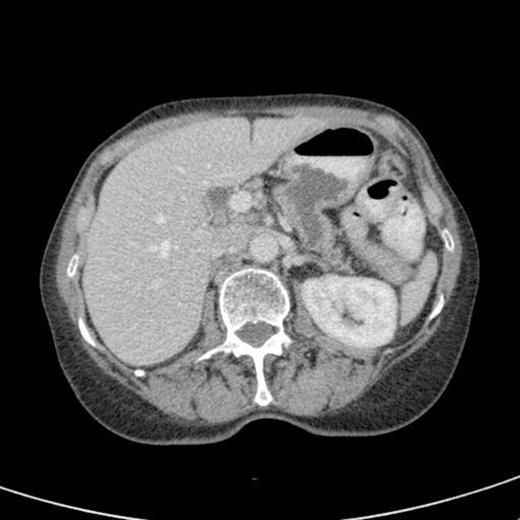

CT scan showing marked dilatation and tortuosity of the main pancreatic duct (12-13mm at the head) with atrophy of the body and tail

CT scan done 2 years later revealed marked dilatation and tortuosity of the main pancreatic duct (12-13mm at the head) with atrophy of the body and tail (Fig1). Repeat scans done on an yearly basis over the next three years reported no progressive change. CT scan done 6 years after the original diagnosis revealed pancreatic duct dilatation to 15 mm with side branch dilatation in uncinate process and atrophic pancreas (Fig 2). A diagnosis of mucinous ductal ectasia or an intraductal papillary mucinous tumour was suggested. On clinical review, patient complained of epigastric discomfort, loose stools, anorexia and weight loss. Upper GI endoscopy and colonoscopy was normal. Faecal elastase was less than 100 confirming pancreatic insufficiency for which she was commenced on creon.